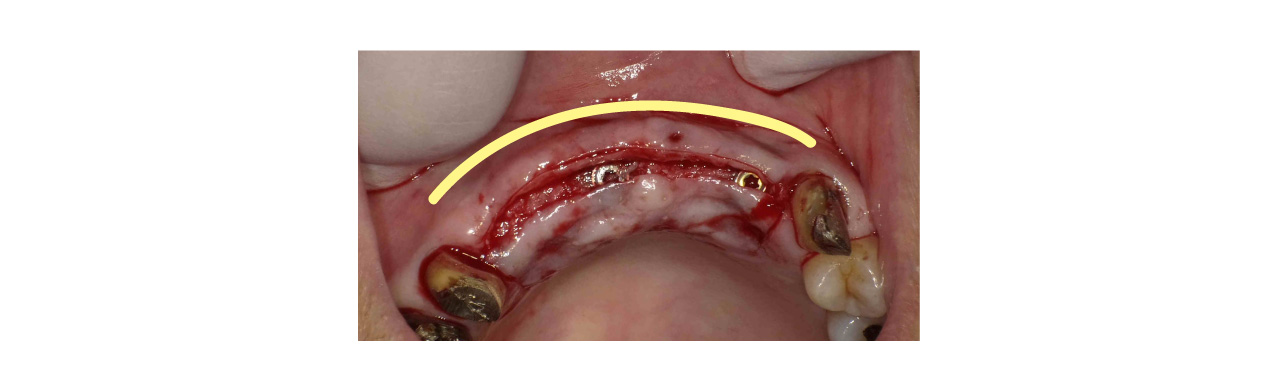

前回お話した角化歯肉を作る処置でも口蓋から歯茎を切り取って移植してましたが、今回は表に貼るのではなく、歯茎の中に移植します。カンガルーの袋の中に入れ込むイメージです

歯茎を詰めたのちに縫合を行います。歯茎を詰めたことにより頬側の歯肉が厚みを増して膨らんでいます。

頬側に折り込まれたことにより頬側の歯肉が厚みを増して膨らんでいるいます。